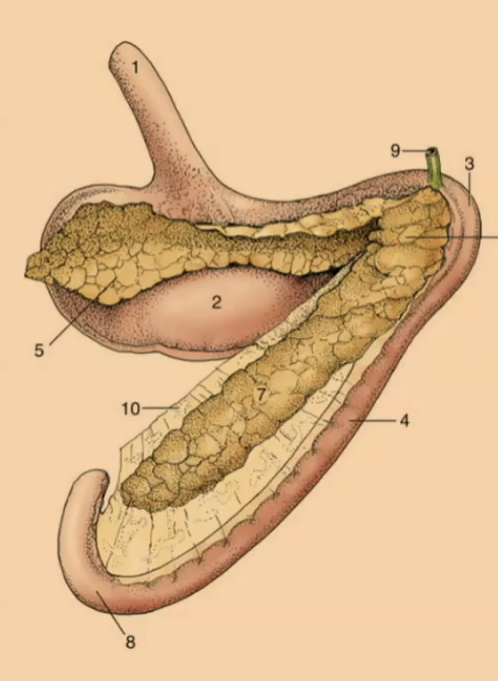

Cecum (top: carnivore; bottom: ruminant)

#4

ileal orifice

#5

Ceco-colic orifice